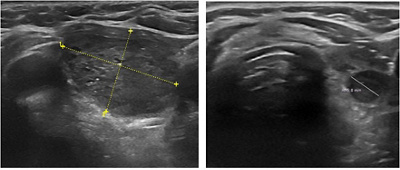

Foto und Sonographie eines Schilddrüsenknotens vor und 6 Monate nach Thermoablation. Der behandelte Knoten zeigt eine Volumenreduktion von ca. 90%.